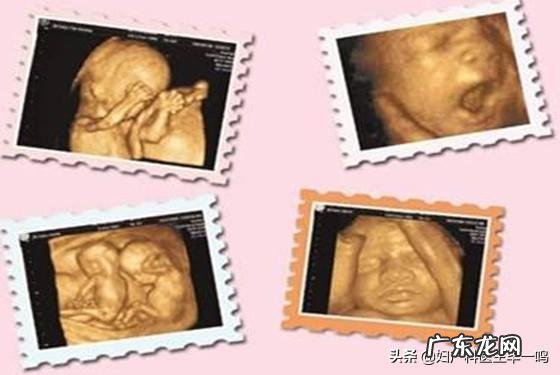

三维彩超形成的图像是立体的 , 可多方位观察胎儿发育情况;四维彩超则更高级 , 是在三维彩超的基础上形成动态的图片 , 可以更清晰的看到胎儿的相貌和动作 。简单来讲 , 三维彩超是静态的 , 四维彩超则是动态的 。不少孕妈在做四维彩超时都会要求刻录一份光盘 , 以此作为留念 。

三维彩超是通过超声诊断仪 , 分别从胎儿不同脏器的不同位置 , 获取若干数据图像 , 经过计算机的快速组合和处理 , 在屏幕上显示出该部位的立体图像 , 三维超声有助于协助诊断胎儿面部异常、神经管缺陷、肿瘤和骨骼畸形等疾病的发生 。

四维彩超又是在三维彩超的基础上增加了时间概念 , 记得胎儿超声增加了实时、动态、立体的更清晰的图像 。

这是立体动态显示的彩色多普勒超声诊断方式 。它不仅具有二维彩超的全部功能 , 还可以进行胎儿头面部立体成像 , 可清晰地显示眼、鼻、口、下颌等状态 , 协助医生直接对胎儿先天畸形进行诊断 , 包括表面畸形和内脏畸形 , 特别是二维彩超难以显示的头面部畸形 , 还能确定胎儿在子宫中的精确位置 。